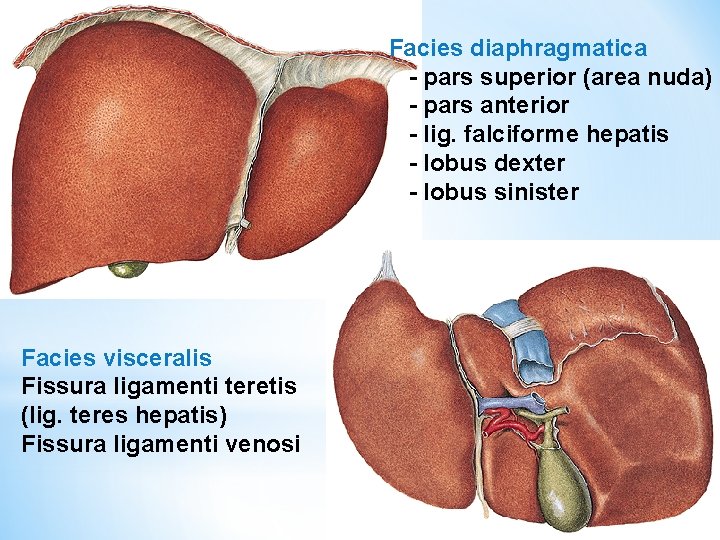

Facies diaphragmatica - pars superior (area nuda) - pars anterior - lig. falciforme hepatis - lobus dexter - lobus sinister Facies visceralis Fissura ligamenti teretis (lig. teres hepatis) Fissura ligamenti venosi